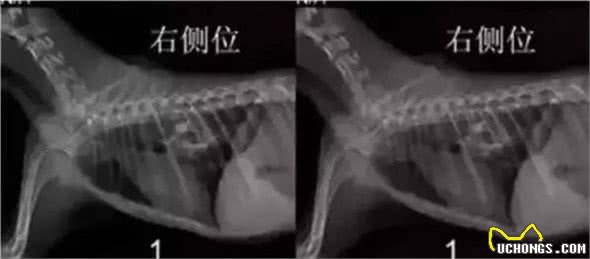

这是医生在抢救一只狗狗,他们经过检查发现狗狗胃里有很多没消化的骨头块,阻塞了肠胃。能够看到狗狗很瘦并且一点精神都没有。经过手术之后从狗狗的胃里取出了3斤的没消化的各色骨头。。。

手术时间长达一个多钟头,如果送赶不及时得话,很有可能就丟了狗命

哈士奇犬由于吃完许多骨头,一块骨头卡在了肠胃了,导致了肠胃阻塞,差点儿就。。。